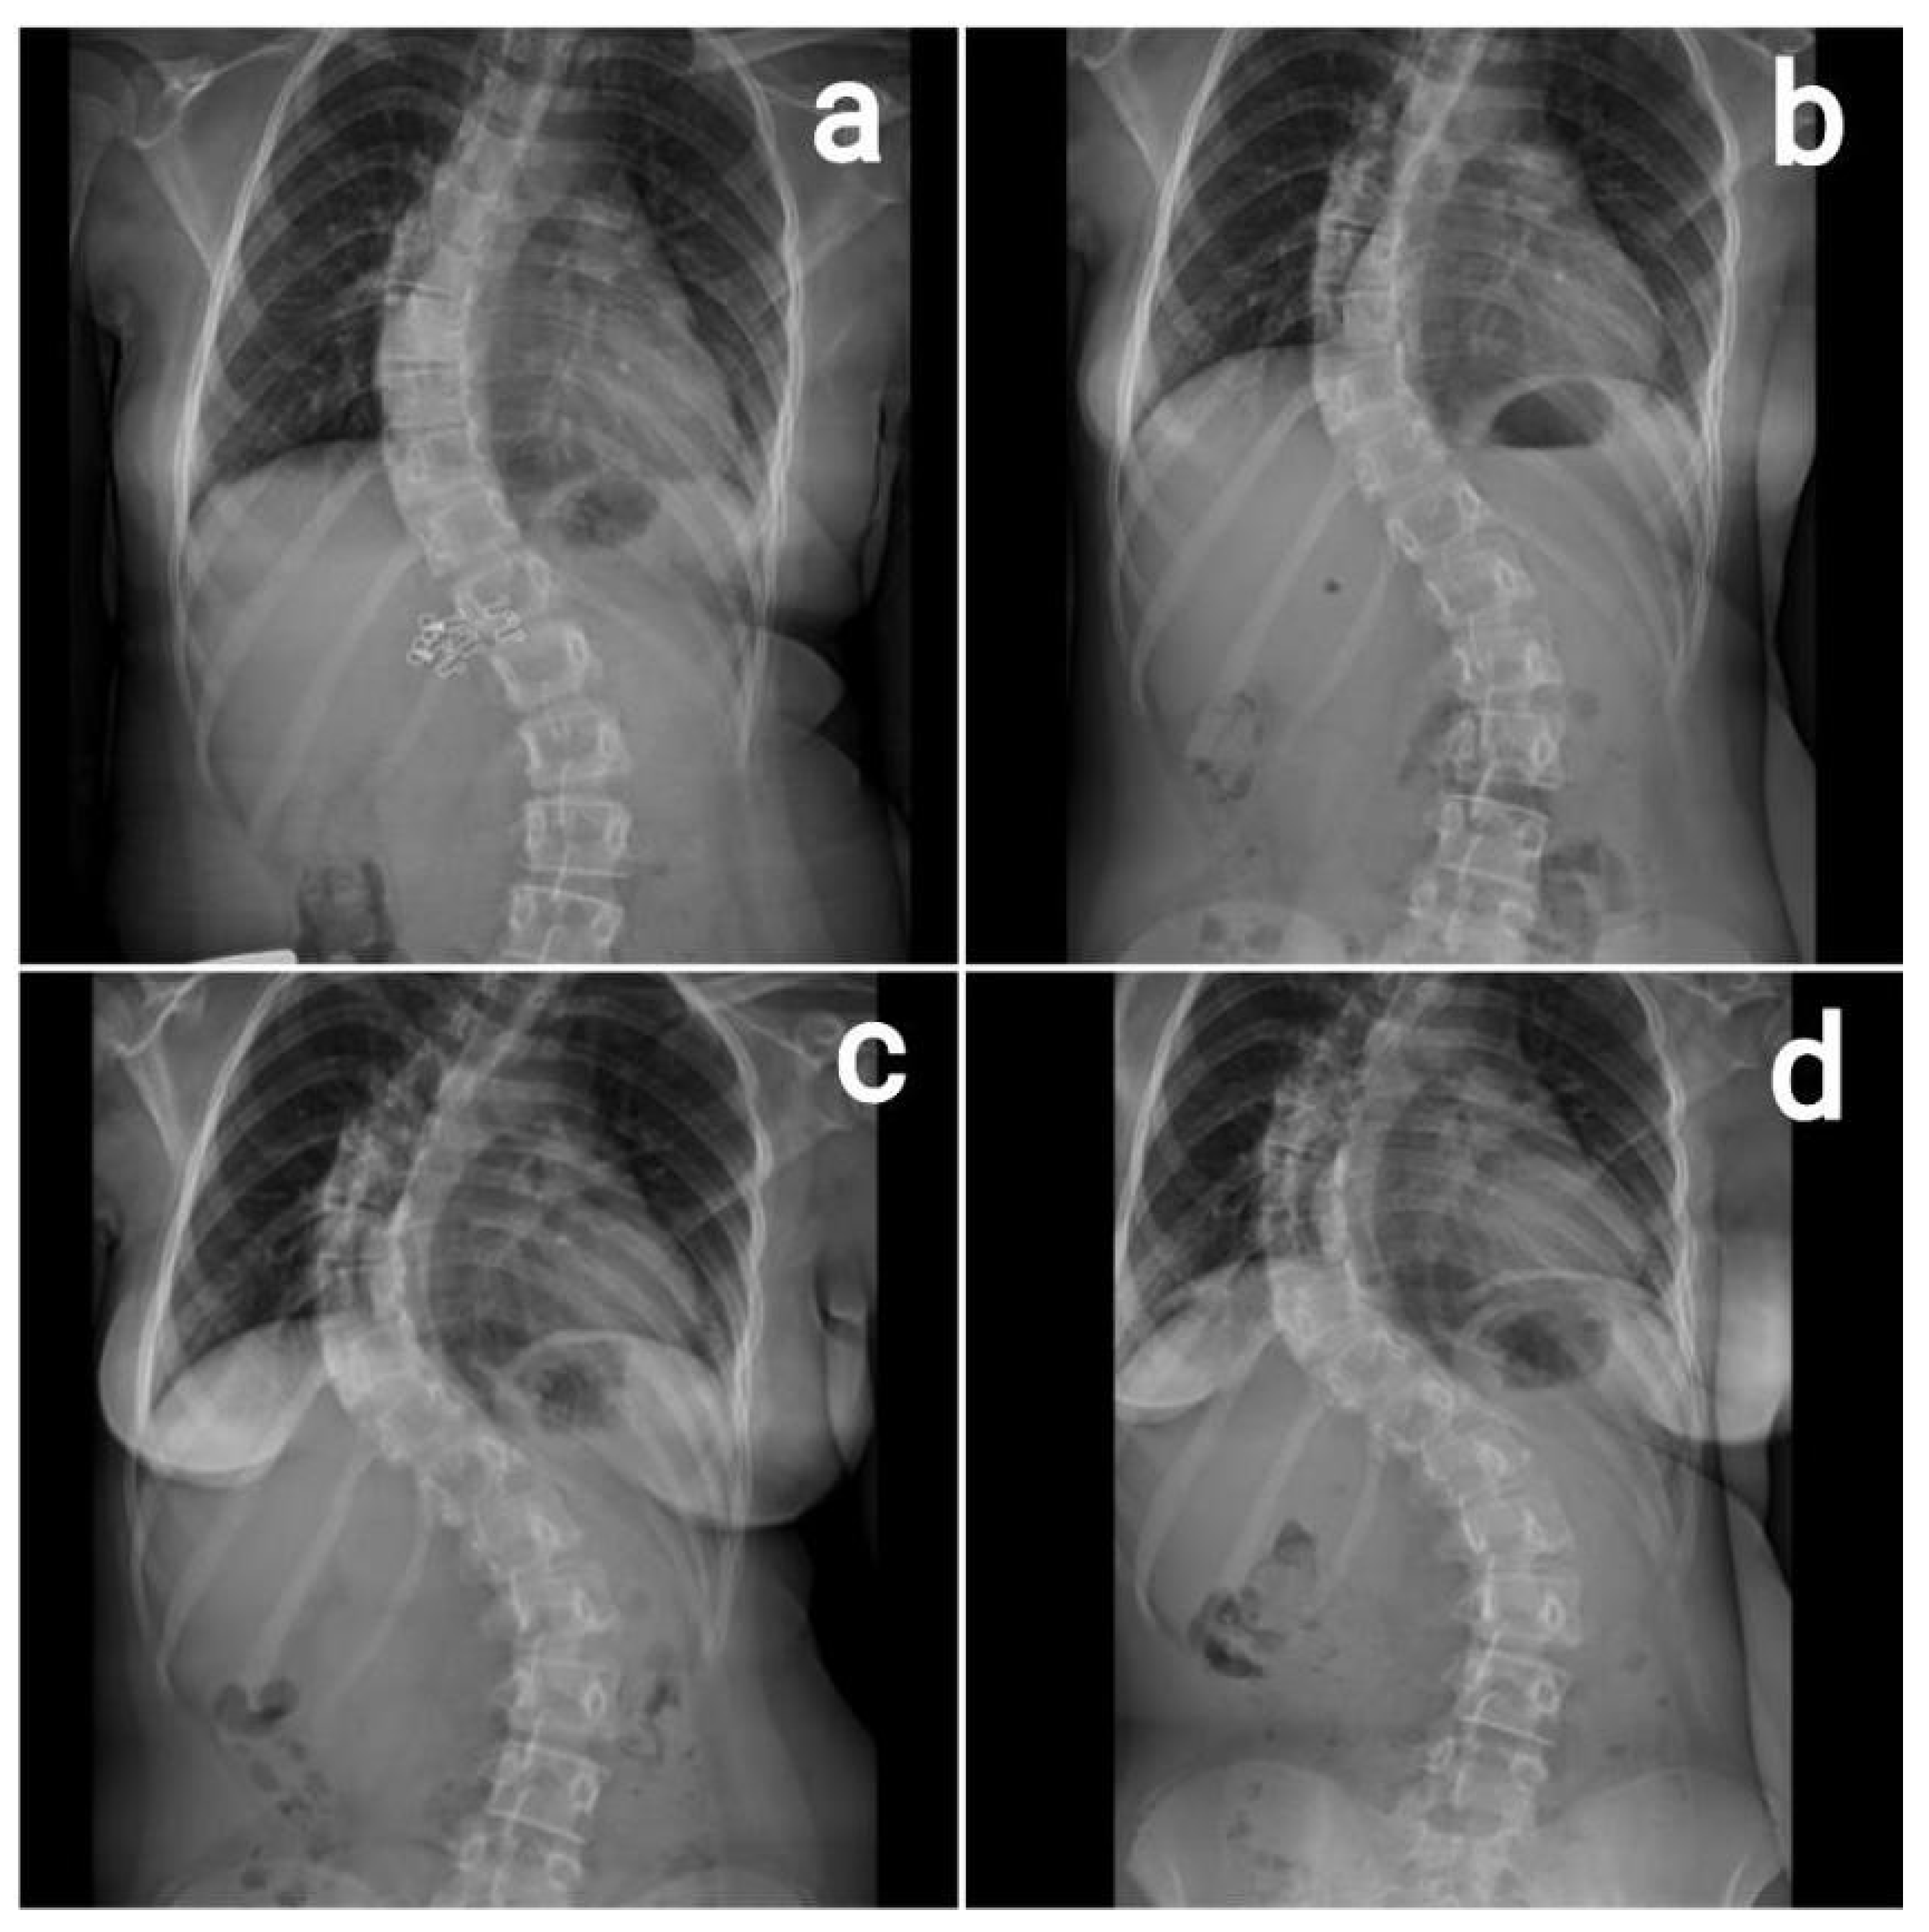

2. Case Report